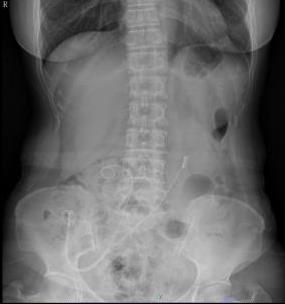

摘要:目的 探讨软式内镜辅助逆行性输尿管导管置入术,对Bricker回肠膀胱术后,输尿管回肠吻合口狭窄即刻再通的疗效。方法 回顾性分析2016年11月-2022年10月该院收治的17例Bricker回肠膀胱术患者的临床资料,共28处输尿管回肠吻合口狭窄,均行软式内镜辅助逆行性输尿管导管置入术治疗。结果 所有患者的总手术时间均 < 50 min。经内镜治疗成功再通的有21处。中位住院时间为6(4.75,8.50)d。28处输尿管回肠吻合口狭窄中,21处内镜下即刻再通成功(左侧10处,右侧11处),7处内镜下即刻再通失败(左侧4处,右侧3处)。21处内镜下即刻再通成功包括:单纯性逆行性置入输尿管导管15处,内镜下输尿管回肠吻合口扩张、网篮取石和逆行性支架置入1处,超细内镜下逆行性输尿管支架置入术3处,十二指肠镜下逆行性输尿管支架置入术2处。17例患者,输尿管支架尿液引流通畅,代膀胱回肠及输尿管回肠吻合口均有不同程度擦伤和少量出血,未发生迟发性出血、穿孔、严重泌尿系感染、支架堵塞和移位等严重并发症。结论 软式内镜辅助逆行性输尿管导管置入术,对输尿管回肠吻合口狭窄的即刻再通,安全且有效。值得应用于临床。